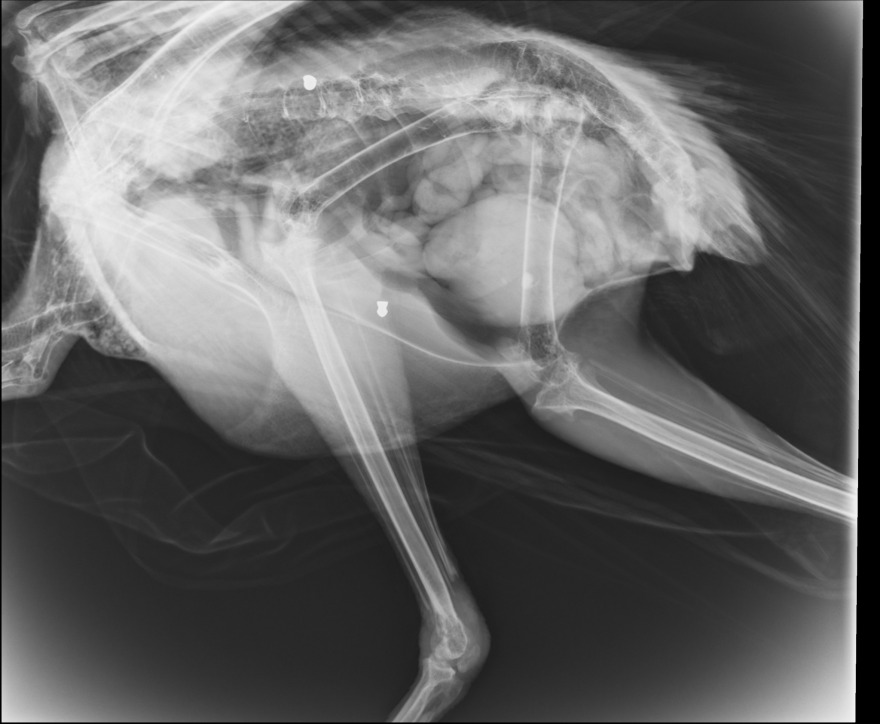

Το γεγονός επιβεβαίωσαν και σχετικές ακτινογραφίες που έδειξαν μάλιστα δυο βολίδες αεροβόλου κι ένα σκάγι.

Δείτε φωτογραφίες: